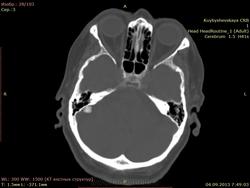

дополнительное образование высокой плотности справа. подскажите

пациентка жалуется на головные боли, больше справа. Подскажите что это за образование справа? первый раз вижу. и деструкции стенки вроде бы нет. плотность высокая.

Остема или небольшая обызвествленная менингиома, что почти одно и тоже. Да менингиому на первое место надо было поставить :)

По-моему обызвествлённая менингиома.

+1. Менингиома.

Стандартное место для менингиомы

Ага, задней грани пирамиды, как некоторые пишут.